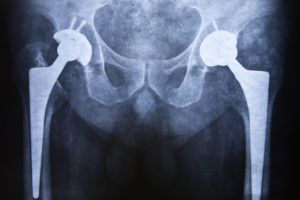

Tips for a Smooth Recovery After a Total Hip Replacement

If your hip arthritis is no longer responding to conservative interventions and has caused extensive damage to the joint, your orthopedic surgeon will likely recommend a total hip replacement (hip arthroplasty) to restore your normal function and mobility. The procedure involves the replacement of a [Read More]

Get to Know Your Joints and How Hip Replacements Work

The hip is among the body’s largest weight-bearing joints. The hip consists of three bones (ilium, ischium, and pubis), and it essentially serves as the junction where the thighbone (femur) joins the pelvis. The hip is a ball-and-socket joint consisting of two main parts—the femoral head (the [Read More]